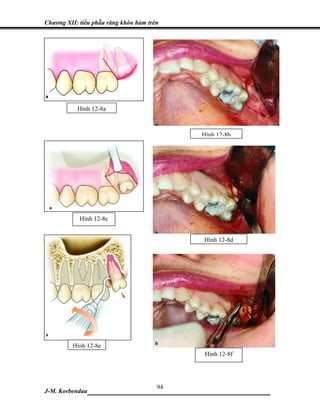

• 113.

100. Kugelberg CF.Periodontal healing two and four years after impacted lower third molar surgery. Int J Oral Maxillofac Surg 1990;19:341–5. 101. Kugelberg CF, Ahlstrom U, Ericson S, et al. The influence of anatomical, pathophysiological and other factors on periodontal healing after impacted lower 3rd molar surgery a multiple-regression analysis. J Clin Periodontol 1991;18:37–43. 102. Grondahl HG, Lekholm U. Influence of mandibular third molars on related supporting tissues. Int J Oral Surg 1973; 2:137–42. 103. Chin Quee TA, Gosselin D, Miller EP, Stamm JW. Surgical removal of the fully impacted mandibular third molar. J Periodontol 1985;56:625–30.